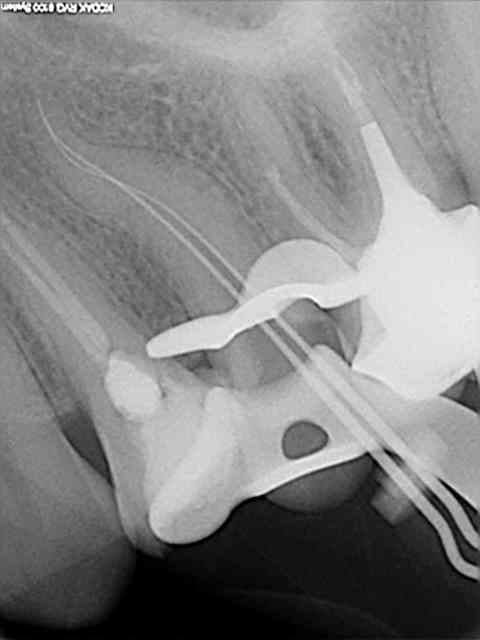

Cas déja posté. F2 neuf cassé dans un canal DL de 36 suite à une petite précipitation à la fin de l'endo.

Dommage car quand on voit la préop et les calcifications, on pouvait se dire que j'avais fait le plus dur.

Le pronostic à long terme n'est pas significativement modifié dans un cas comme celui-là (champ op, symptomalogie pré-endo seulement inflammatoire, casse en fin de préparation et après bonne irrgation); et de toute façon, impossible de retirer l'instrument.

C'est vraiment con cette casse car j'avias fait le plus dur en redressant bien comme il faut les triangles dentinaires mésiaux à l'entrée des canaux.

Tout ça parce que l'AD où je faisais le rempla m'avait collé une urgence "entre deux" juste avant la bio. De ce fait, j'étais un peu à la bourre et bing! Le pire c'est que l'urgence en question était un casse bonbon de première. Grrr!